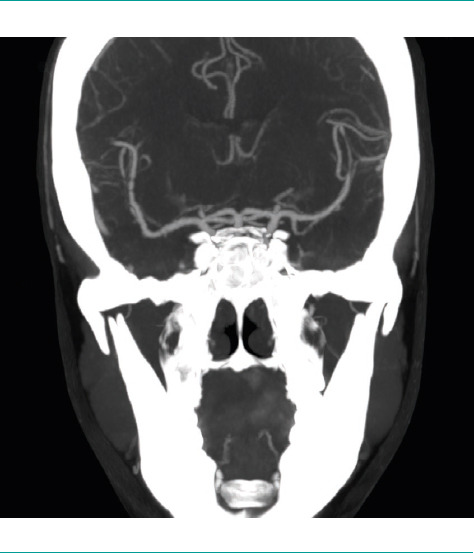

Case report: A 44-year-old woman with a history of multiple sclerosis treated with interferon beta-1b who had four episodes of thunderclap headache while resting, after completing a course of corticosteroids due to a flare-up of optic neuritis. Three years earlier, the patient had presented several episodes of explosive-onset headache during a self-limited period of one month, only occurring during sexual intercourse. In the year prior to our assessment, she had suffered three thunderclap headaches with similar characteristics, but they were triggered only by intense physical exercise. She had not consulted a physician about these events. A cranial computed tomography scan was performed after the administration of contrast media and a cerebral arteriography, which were consistent with cerebral vasoconstriction syndrome, and its reversibility was confirmed three months later.